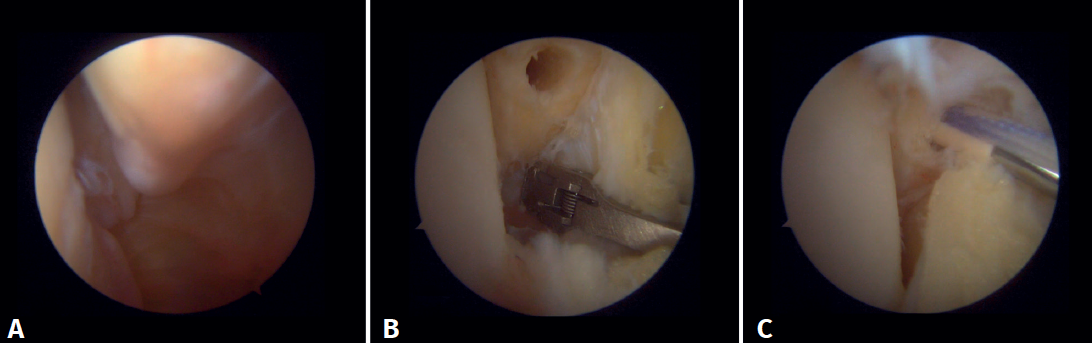

Técnica quirúrgica: tratamiento artroscópico de las lesiones agudas de la sindesmosis

La técnica se realizará utilizando los portales anteromedial y anterolateral convencionales. El portal anteromedial se emplea para la visualización, mientras que el portal anterolateral sirve como portal de trabajo. Una vez visualizado el espacio tibioperoneo, resecaremos la sinovial inflamada con un shaver artroscópico para facilitar la reducción (Figura 7A). Posteriormente, mediante visión directa restauraremos el espacio tibioperoneo, teniendo muy en cuenta la posible malrotación del peroné, especialmente en fracturas de tipo Maisonneuve. Para la reducción peronea utilizamos una pinza de tipo Verbrugge que nos permite corregir la rotación. En nuestra experiencia, una vez limpiado el espacio y si la posición es correcta, es poco frecuente tener que utilizar una pinza compresora entre tibia y peroné.

Para la fijación definitiva, las opciones quirúrgicas varían entre una fijación rígida con tornillos y una fijación dinámica. Los tornillos han sido el procedimiento estándar durante décadas, pero presentan complicaciones, como aflojamiento o rotura. Además, algunos cirujanos defienden su retirada, con el riesgo inherente de recurrencia de la inestabilidad(27). La fijación dinámica se diseñó para solventar algunos de estos problemas, al permitir cierto movimiento fisiológico de la sindesmosis, facilitar la carga temprana, reducir el riesgo de rotura y eliminar la necesidad de extraer el implante (Figura 7B).

Grassi et al., en un metaanálisis con más de 300 pacientes, demostraron una disminución global del riesgo relativo de complicaciones (RR = 0,55; p = 0,003) con sistemas dinámicos(28). Raeder et al., en un ensayo aleatorizado de 97 pacientes entre fijación con tornillos y sistema dinámico, demostraron una menor incidencia de artrosis con suture button del 65 vs. 35% (p = 0,009) a los 5 años(29). Las construcciones con suture button aportan cierto grado de micromovilidad, imitando la movilidad fisiológica, que puede favorecer la cicatrización ligamentosa. Asimismo, los implantes flexibles toleran mejor una reducción imperfecta, una complicación posible, aunque realicemos un control artroscópico de la articulación.

Técnica quirúrgica: tratamiento artroscópico de las lesiones agudas del complejo medial

En cuanto a la técnica quirúrgica, los portales de trabajo se realizarán de la misma manera que en una artroscopia de tobillo convencional: un portal anteromedial y uno anterolateral. Se inicia siempre con una artroscopia diagnóstica para confirmar la lesión del ligamento deltoideo. Puede utilizarse un palpador para verificar la laxitud de las fibras y realizar una prueba con este introduciéndolo a través de la gotera medial: si pasa, confirma la lesión. Para la reparación, el portal de visión será el anterolateral, así se trabajará de forma más directa a través del anteromedial. Las fibras anteriores del tibiotalar superficial e intermedias de la porción profunda del deltoideo son las que la técnica artroscópica permite reparar(38). Una vez identificado y disecado el ligamento, se pasa una sutura entre las fibras mediante un pasador de sutura. Se prepara la zona de anclaje del maléolo medial con un rasurador o una pequeña fresa. Con el tobillo en posición neutra se introduce el ancla manteniendo la tensión de las suturas. Se puede utilizar como referencia anatómica para la colocación la intersección de la línea paralela a la articulación tibiotalar y una línea perpendicular marcada desde la punta del maléolo y por el borde lateral de este(21). Tras realizar la reducción, se prueba nuevamente la tensión de las fibras y el paso del probador por la gotera medial, que confirma una adecuada reparación (Figura 8).

Figura 7. A: desbridamiento del espacio tibioperoneo; B: estabilización de la sindesmosis mediante sistema de suspensión.